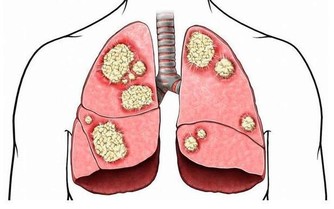

人們都說肝病猛於虎,如果患上肝病又沒有及時治療的話,很容易就會發展成肝硬化,更嚴重就會轉變為肝癌,增加了治療的難度,甚至危及到生命健康。肝病患者只要積極的配合醫生治療,就能夠延緩向肝癌發展的進程。其實比起治療肝病,做好肝病的預防更能從源頭上切斷患病機率,而且飲食調理至關重要。

肝硬化是臨床常見的慢性進行性肝病,由一種或多種病因長期或反復作用形成的瀰漫性肝損害。在我國大多數為肝炎後肝硬化,少部分為酒精性肝硬化和血吸蟲性肝硬化。